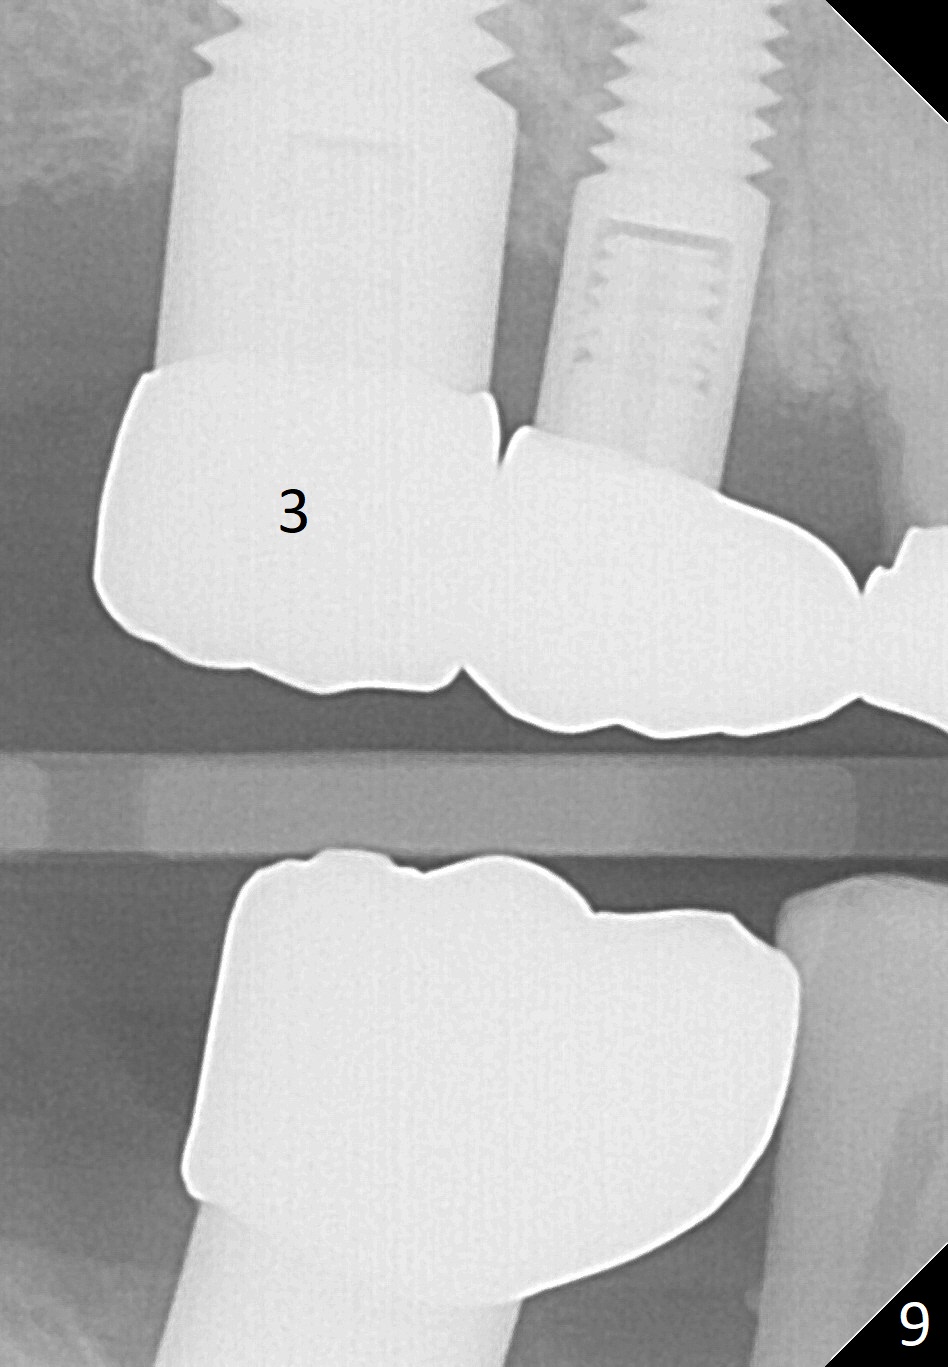

The implant at the site of #3 is intentionally placed distal as part of a plan to distalize the teeth #4-6 (Fig.1). Ortho started, but the patient did not want to pursue it. The most efficient way to terminate it is to dislodge every one of brackets/bands. When it is time for restoration for implants at the sites of #3 and 30, it is a challenge to deal with the space mesial to #3. The patient is planning to leave the country in 20 days. Fortunately he agrees to have an extra implant (Fig.2). It must be small in diameter. The initial osteotomy does not go on smoothly, approaching the apex of the tooth #4 (Fig.3 A). The osteotomy is moved distally and the trajectory is changed. It appears to be overcorrected (Fig.4). After re-adjustment, a 3.5x14 mm implant is placed with insertion torque between 15 and 20 Ncm (Fig.5). An abutment is placed with perio dressing applied around it as well as #3 after suturing. When the wound heals and before the patient leaves the country, the abutment is removed.